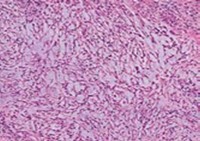

Ultrastructural evaluation is devoid of pertinent cellular features. However, modified endothelial cells, smooth muscle cells, striated muscle cells, histiocyte- like cells, fibroblast- like cells and miniature, interdigitating cellular processes conjoined by desmosome- like junctions are discerned5, 6. Figure 1, Figure 2, Figure 3, Figure 4, Figure 5, Figure 6, Figure 7, Figure 8.

Figure 1.Angiomatoid fibrous histiocytoma demonstrating a multinodular pattern with circumscribing lymphoid and plasma cell infiltrate and a superimposed stratified squamous epithelium 9